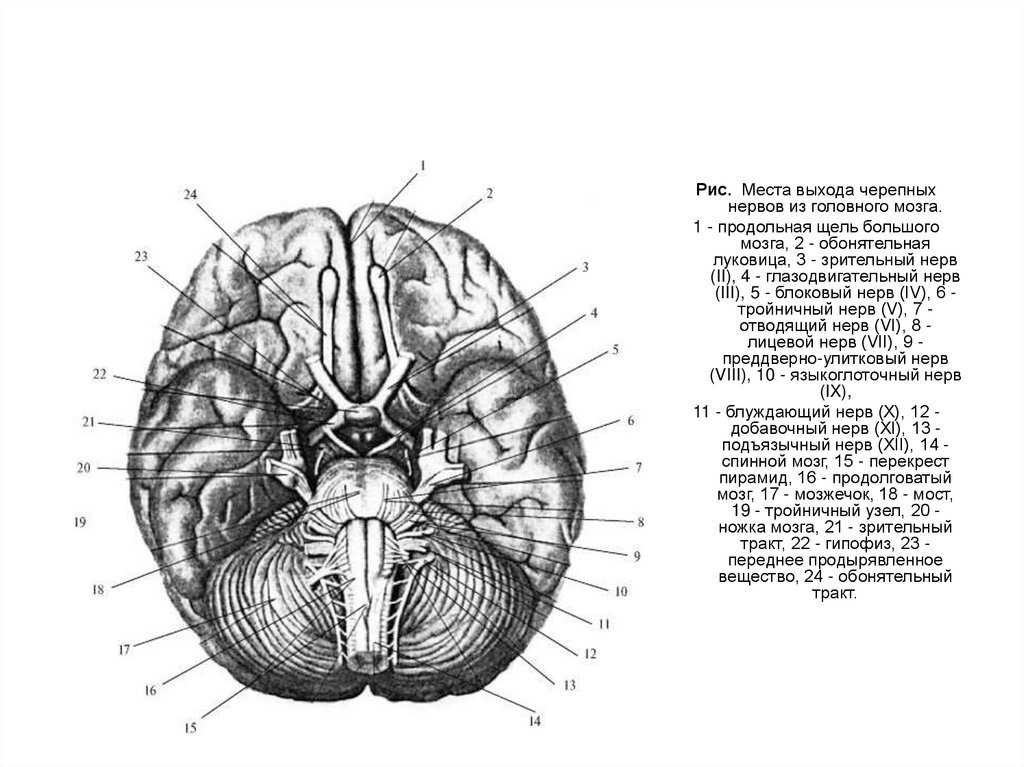

Легкие рисунки головного мозга: Пошаговые инструкции